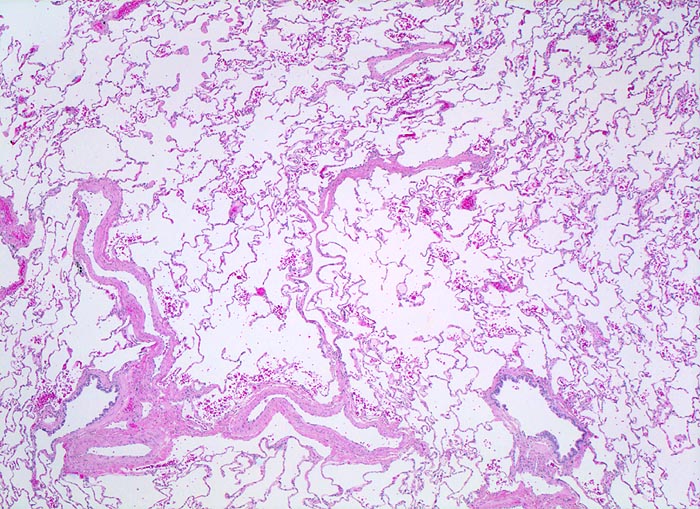

PathoPic – image database / PathoPic ID 4367 - normales Lungenparenchym

normales Lungenparenchym

Die Lungenarterienäste verlaufen zusammen mit den respiratorischen Bronchiolen. Die Lungenvenenäste verlaufen dagegen unabhängig von den Luftwegen im Parenchym. Die Alveolarsepten sind zart. In den Alveolen findet sich entnahmebedingt etwas Blut.